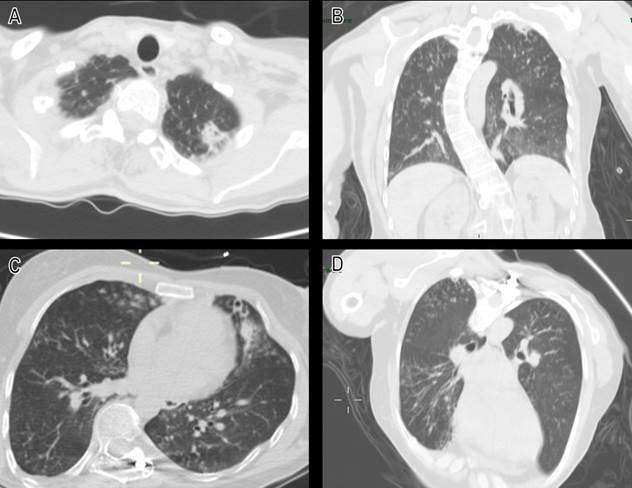

A chest CT scan showed the presence of cavitating lesions on the apical lobes associated to centrilobular nodules, reticulonodular infiltrates (Figure 2A,B) and the previously known cylindrical bronchiectasis (Figure 2C,D). HIV, VDRL, 3 blood cultures set, urinary Histoplasma antigen, serum galactomanan, and interferon-gamma release assay were all negative. Transesophageal echocardiogram ruled out infective endocarditis. The patient underwent a surgical excision of the lesion, and tissue was sent for Tb PCR (GeneXpert®), 16S RNAr sequencing, histopathology, as well as for bacterial, mycobacterial, and fungal cultures.

As stated earlier, there is a well described association between Nocardia and bronchiectasis. In the context of pulmonary nocardiosis, bronchiectasis is the second most commonly reported predisposing respiratory condition (29-38%).3 This association seems to be strong enough to have epidemiological implications. For example, a study from Duke University Hospital reported a significantly increase in Nocardia incidence over time, which appears to be driven by an increased incidence in patients with bronchiectasis rather than increases in immunocompromised populations.3 Due to this important association and the ruling-out of endocarditis, direct inoculation and contiguous infection as possible causes, the bronchiectasis that our patient presented were deemed to be most likely source of infection. Pulmonary nocardiosis could not be confirmed due to the fact that the patient did not produce a suitable sputum specimen.